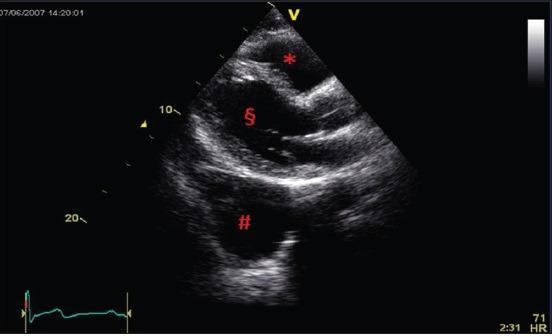

Pericardial cysts, an uncommon benign congenital anomaly belonging to the category of mediastinal masses. Cysts are usually detected incidentally on chest radiography or echocardiography, being most patients asymptomatic. In some cases, however, symptoms and complications occur, like dyspnea, chest pain, or persistent cough. Computed tomography and magnetic resonance imaging are the imaging techniques of choice to diagnose pericardial cysts. The removal of pericardial cysts is restricted to the cases with an uncertain diagnosis or in the presence of symptoms.

心包囊肿是一种罕见的良性先天性异常,属于纵隔肿物范畴。囊肿通常在胸部X线摄影或超声心动图检查时偶然发现,大多数患者无症状。然而,在某些情况下会出现症状和并发症,如呼吸困难、胸痛或持续性咳嗽。计算机断层扫描和磁共振成像为诊断心包囊肿的首选成像技术。心包囊肿的切除仅限于诊断不明确或有症状的病例。